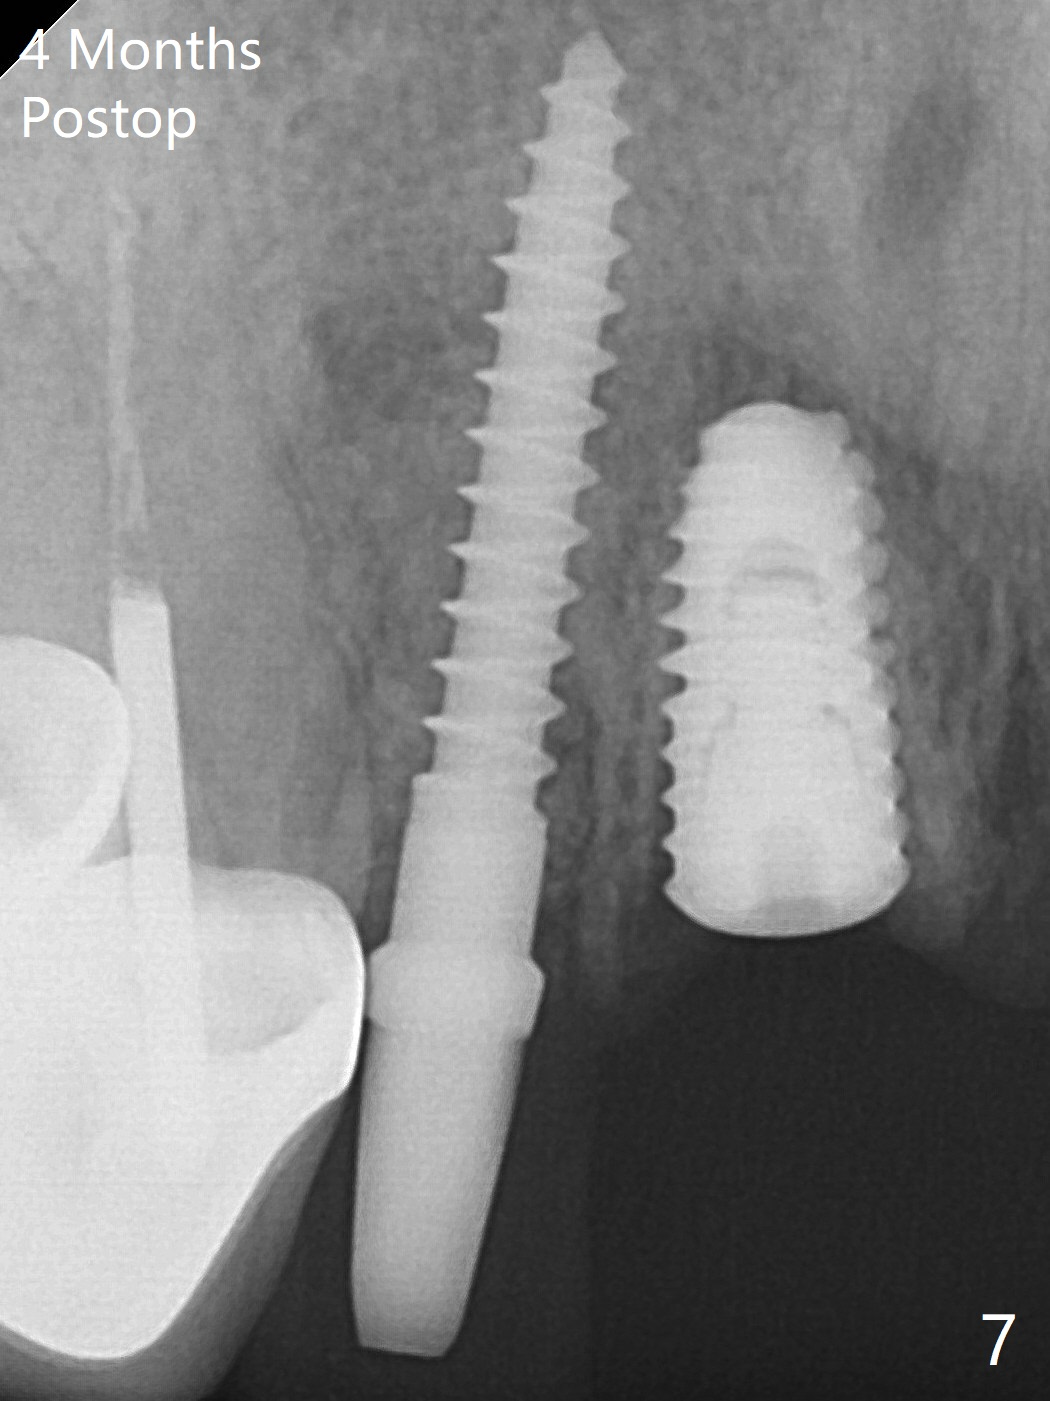

Because of the long crowns of the neighboring teeth, it is difficult to remove the apical portion of the root, including gutta percha with surgical handpiece (Fig.3 * (1.2 mm drill for 12 mm)) for socket shield. To avoid the perspective implant touching socket shield, initial osteotomy is palatal. When a 2 mm drill is being used, the coronal end of the palatal plate starts to perforate. A 2.5x14 mm 1-piece implant is placed with 30 Ncm (Fig.4). The teeth #8 and 9 fracture (an implant is placed at #8 and bone graft at #9), while the implant at #7 is osteointegrating (Fig.7). In fact the shield is exposed without symptom.